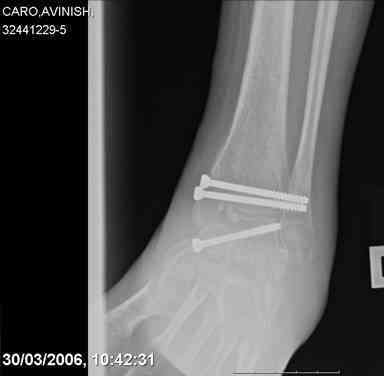

ya by popytalsya sobrat talus anatomichno,seichas pozdno operirovat iz za oteka,po etomy distrakziya apparatom budet optmalna.Posyalu vam podobyai moi sluchai.

14 years old girl

Fall from height ( 3rd floor)

Compressed fractures of L1-L2

Fx of orbital bone

Дорогие Mark Eidelman and A. Liberson. Спасибо за представленные иллюстрации и за дельные советы.

Mark, судя по снимкам в день поступления произведен А.В.Ф., а остеосинтез ч-з какое время произведен?, остеосинтез произвели открытым способом?( на снимке п/о рубцы).

aparat postavlen v den postupleniya,rastaynuli, vpravili zakryto naskolko vozmoghno, a kogda otek spal sdelali otkrytoe vpravlenie.Teryat tut nechego, moghno tolko uluchshit.